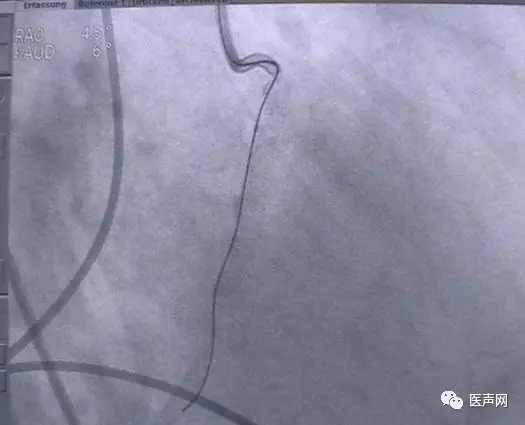

病例4:LAD PCI术后,对角支远端病变

此病变上次PCI不成功,因为LAD有支架,导丝穿过支架网眼入对角支有困难(对角支发出角度很大,成直角(箭头所示)。此次不再尝试,要学会放弃。

见下图: